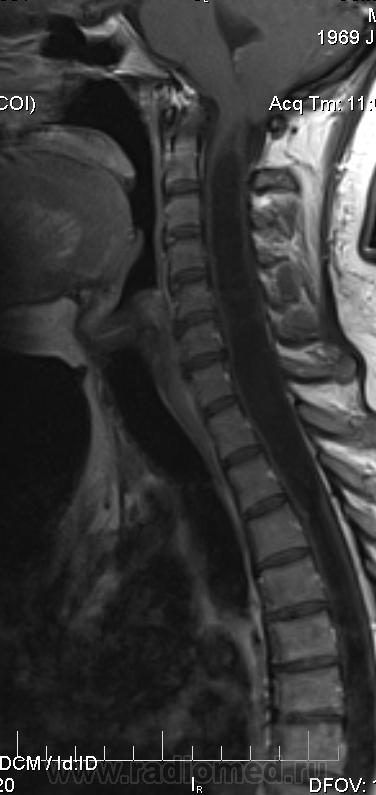

Сирингомиелия шейно-грудной локализации? Аномалия Арнольда-Киари I. Платибазия.

Убедительных данных за патологическое накопление контрастного препарата не выявлено. Кисты с повышенным содержанием белка (?), может быть бывают атеромы в области мягких тканей шеи (гиперинтенсивные по Т1 между мышцами шеи справа)?

здоровенная сирингогидромиелитическая киста (по видимому, "высокого давления"), мальформация Киари 1.   также имеются признаки внутренней окклюзионной гидроцефалии.

Cпасибо большое, как вы думаете, это  кисты в области мягких тканей шеи справа (гиперинтеснивные по Т1 и Т2), или что-то другое?

морфологически- явно кистозные образования. А вот их происхождение - вопрос.